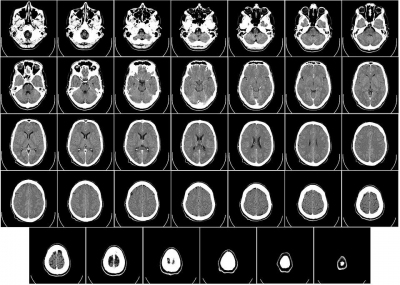

Ricerca. Demenza precoce, uno studio lega i sintomi cognitivi e psichiatrici con le alterazioni delle strutture cerebrali

La ricerca, su 150 pazienti, è frutto di una collaborazione italo-olandese che si è sviluppata al Policlinico di Milano. I risultati potrebbero migliorare la diagnosi dei pazienti con Demenza Fronto...